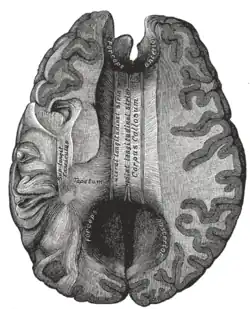

![]() Sagittal section of brain, front part to the left. The corpus callosum can be seen in the center, in light gray | |

The corpus callosum (Latin for "tough body"), also callosal commissure, is a wide, thick nerve tract, consisting of a flat bundle of commissural fibers, beneath the cerebral cortex in the brain. The corpus callosum is only found in placental mammals.[1] It spans part of the longitudinal fissure, connecting the left and right cerebral hemispheres, enabling communication between them. It is the largest white matter structure in the human brain, about 10 in (250 mm) in length and consisting of 200–300 million axonal projections.[2][3]

The corpus callosum forms the floor of the longitudinal fissure that separates the two cerebral hemispheres. Part of the corpus callosum forms the roof of the lateral ventricles.[5]